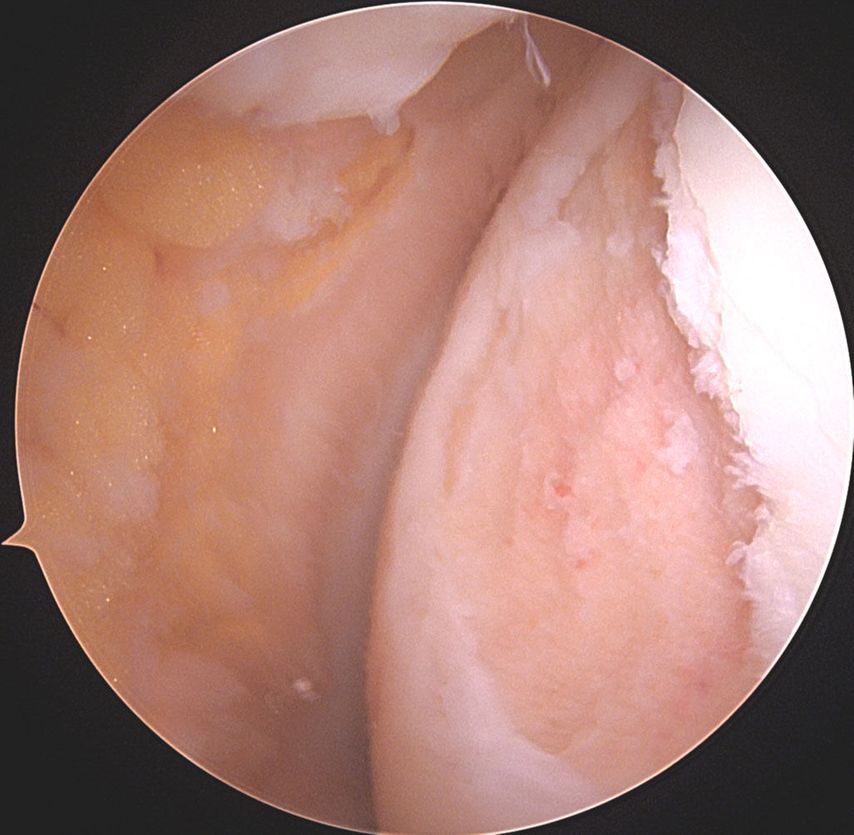

Abb. 1c: Intraoperatives arthroskopisches Bild des Knorpeldefektes nach Debridement an der medialen Femurkondyle Knie links, Defekt 2 x 3cm = 6cm2